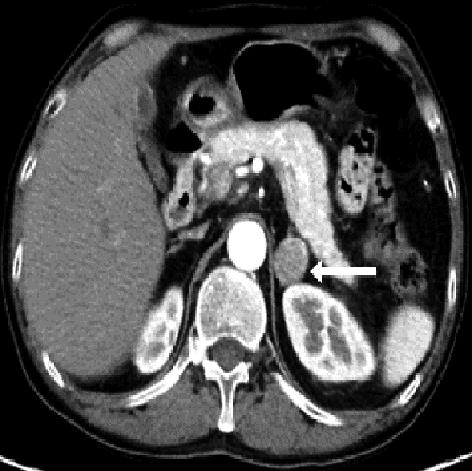

• 嗜铬细胞瘤及副神经节瘤不同生化表型的CT征象对比研究

2024, 49(2):203-209. DOI: 10.13406/j.cnki.cyxb.003433

摘要 (51) HTML (33) PDF 3.10 M (96) 评论 (0) 收藏

摘要:目的 分析生化阴性嗜铬细胞瘤及副神经节瘤(pheochromocytomas and paragangliomas,PPGLs)的电子计算机断层扫描(computed tomography,CT)征象是否有别于生化阳性PPGLs,同时了解生化阳性PPGLs不同表型的CT征象是否存在差异。方法 回顾性分析131例PPGLs患者的术前腹部增强CT图像,包括肿瘤位置、大小、形态、囊变坏死、液-液分层、钙化、向心结节状强化、肿瘤内粗大血管、强化包膜、绝对廓清率及相对廓清率。根据生化水平,将患者分为生化阳性组和阴性组,阳性组进一步分为去甲肾上腺素型、肾上腺素型及多巴胺型。比较各组及各表型间的CT征象差异。结果 相较于生化阴性组,阳性组PPGLs更大(Z=-2.064,P=0.039)、囊变坏死(χ2=6.610,P=0.010)及向心结节状强化(χ2=3.909,P=0.048)的比例更高;相较于去甲肾上腺素型,肾上腺素型PPGLs更大(Z=-2.036,P=0.042)、强化包膜比例更高(χ2=7.242,P=0.007)。结论 肿瘤大小、囊变坏死及向心结节状强化的CT征象有助于术前诊断生化阴性PPGLs,肿瘤大小及强化包膜有助于解释去甲肾上腺素型及肾上腺素型PPGLs不同临床表现产生的机制。